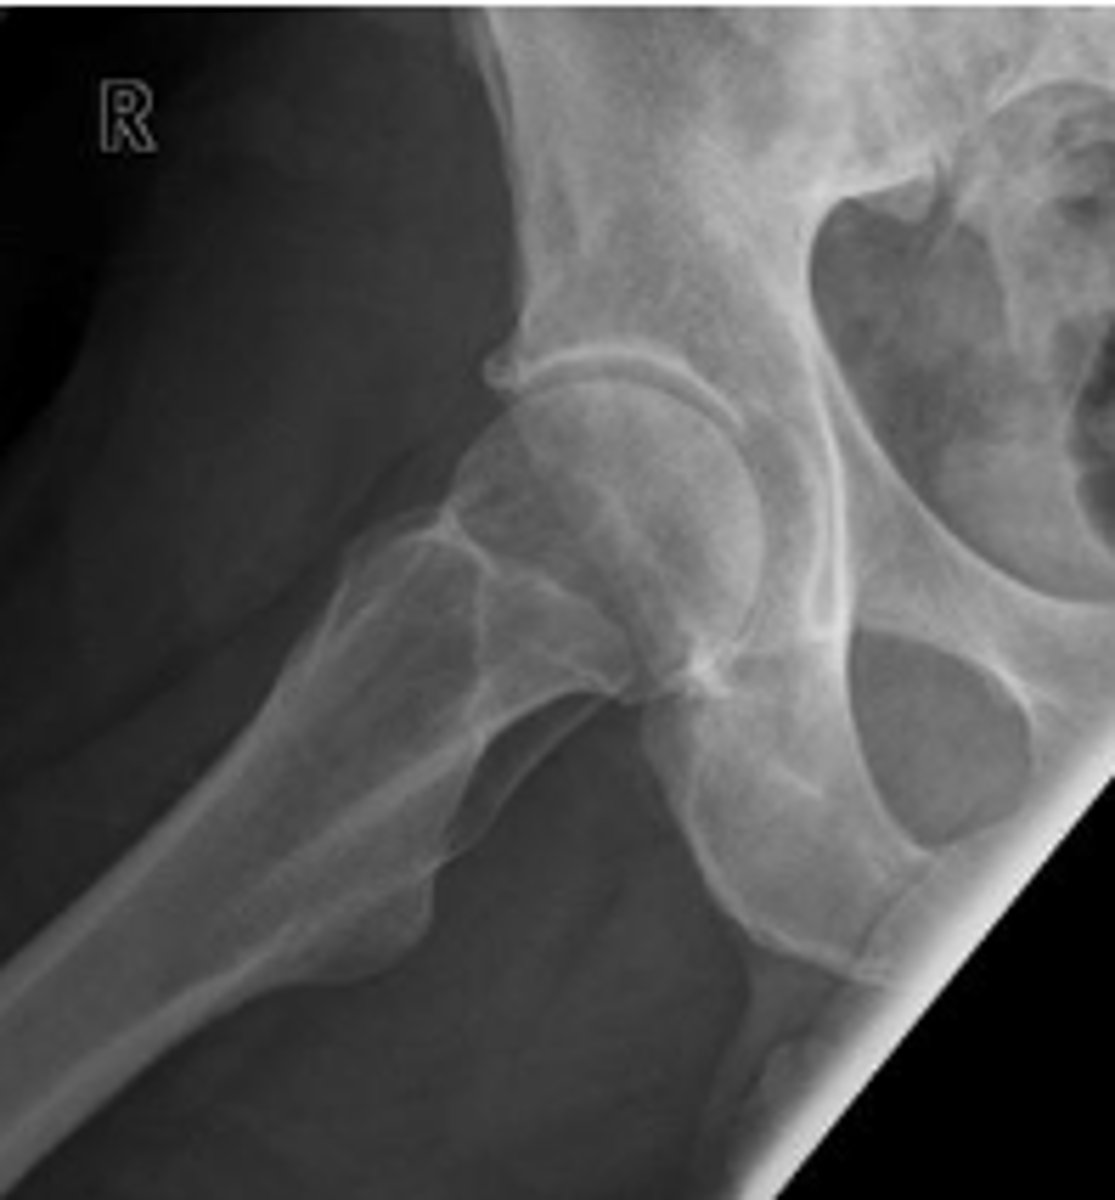

Pubic symphysis width

What is the name of the assessment?

3.8-6mm (average of 5mm)

What is the normal range for this assessment in women?

The distance between the articular surfaces of

the middle of the pubic symphysis

What are the osseous landmarks for this assessment?

No

Is the measurement within normal limits?

Post-traumatic diastasis, inflammatory resorption

Name 2 conditions that may result in a measurement of 12 mm?

AP pelvis or bilateral hips

Name the radiographic view

Shenton's line

From the undersurface of the femoral neck

continued to the inferior aspect of the superior

pubic ramus

What are the osseous land marks for this assessment?

Hip dislocation, fracture

Name 2 conditions that may result in an abnormal assessment?

Posterior hip dislocation

What is most significant radiographic finding?

Femoral angle

120-130 degrees

What is the normal range for this assessment?